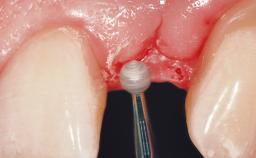

A 42-year-old female patient was referred to our clinic at the School of Dentistry of the University of São Paulo in November 2004, presenting a deficient restoration in the upper left central incisor. The clinical examination revealed no gingival retraction or any signs of gingival inflammation and, therefore, previous periodontal treatment was not considered. The patient presented a high lip line at full smile and a thin tissue biotype. This combination characterized a high-risk situation from an anatomic point of view, which required careful preoperative planning and cautious surgical execution.

Placement Protocol Immediate implant placement

Tooth Site Maxillary incisor or canine

Socket Morphology Single-root socket

Socket Integrity Sufficient, with intact bone walls